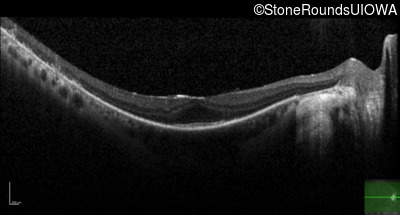

Optical Coherence Tomography - Right - 20/25 -2 sc

Exemplar / OCT Stack

OCT Stack